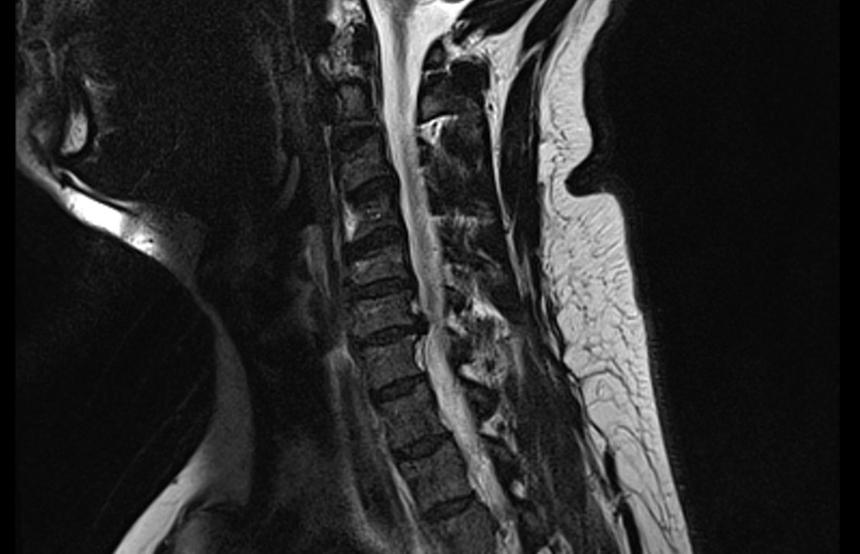

Некоторым пациентам с грыжей межпозвоночных дисков стоит подождать с операцией — во многих случаях она исчезает через два месяца, рекомендовал врач Алексей Исайкин.

Симптомные грыжи межпозвоночных дисков за период от двух месяцев до года рассасываются в 60-70% случаев, заявил сотрудник Первого Московского Государственного медицинского университета им. И.М. Сеченова Алексей Исайкин.

При этом бессимптомные грыжи исчезают максимум в 18% случаев, отметил врач. В среднем срок рассасывания острой грыжи составляет от двух месяцев до одного года. При этом предсказать, произойдёт ли резорбция грыжи, нет, отметил специалист.

Радикулопатия возникает не только от сдавливания грыжей спинномозговых корежков, но и в результате воспаления, подчеркивает Исайкин. Симптомы синдрома — онемение в пальцах, боль в спине, «прострелы» — уходят через три-шесть недель, в сама грыжа начинает уменьшаться через два месяца. Поэтому, советует невролог, имеет смысл не удалять грыжу сразу, а подождать какое-то время и ограничиться консервативным лечением.